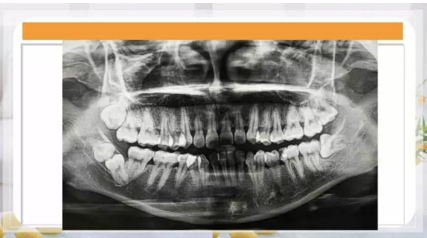

智齒區(qū)多生牙

9.png